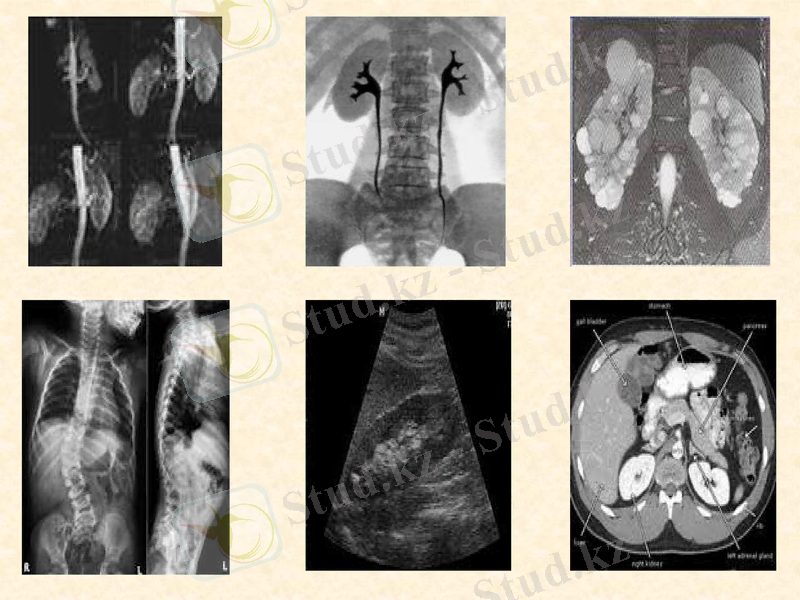

Экскреторлық урография зақымдалған бүйректің ғана емес, контралатеральдық бүйректің де функциялық қабілеттерін бағалауға мүмкіндік береді.

Рентгенологиялық тексеру бүйрек маңында гематома болған жағдайда диафрагма күмбезінің жоғары орналасқаны, бүйрек өңіріне жайылып таралған гомогендік көлеңкені, бел бұлшықеті мен бүйрек контурларының анық еместігі не мүлдем жоқтығы, ішек тұзақтарының парезі салдарынан газ кернеп көбіне қарама-қарсы жаққа жылжуы байқалады.

Көктамыр пиелоуретерография-нефроэктомия көрсеткіші болып табылады.

Ретроградты пиелография кезінде зақымдалған бүйректің қуыстарында жасалатын көтеріңкі қысымның нәтижесінде оның өз капсуласының шегіндегі, сондай-ақ бүйрек маңы кеңістігіндегі контрасттық зат іркілістерін анықтауға болады.

Артериография-қансыраған тамырларды, бүйрек артерияларының негізгі тармақтарының окклюзиясын, сонымен қатар бүйрек жыртылуын анықтауға мүмкіндік береді.

Бүйрек ангиографиясы

Сцинтография

УДЗ